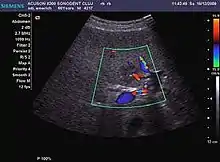

It is a tumor developed secondary to a circulatory abnormality with abundant arterial vessels having a characteristic location in the center of the tumor, within a fibrotic scar. A radial vessels network develops from this level with peripheral orientation. The tumor's circulatory bed is rich in microcirculatory and portal venous elements. The incidence is higher in younger women and tumor development is accelerated by oral contraceptives intake. 2D ultrasound appearance is a fairly well-defined mass, with variable sizes, usually single, solid consistency with inhomogeneous structure. Rarely the central scar can be distinguished. Spectral Doppler examination detects central arterial vessels and CFM exploration reveals their radial position. CEUS examination shows central tumor filling of the circulatory bed during arterial phase and completely enhancement during portal venous phase. During this phase the center of the lesion becomes hypoechoic, enhancing the tumor scar. During the late phase the tumor remains isoechoic to the liver, which strengthens the diagnosis of benign lesion.

Spectral Doppler characteristics of early HCC overlap those of the dysplastic nodule, as they are represented by the presence of portal venous signal type or arterial type with normal RI (well differentiated HCC) or increased RI (moderately or poorly differentiated HCC). The CFM exploration identifies a chaotic vessels pattern.